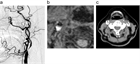

1. 典型症例として症候性内頚動脈狭窄について画像を用いて解説した。詳細は本文を参照されたい。